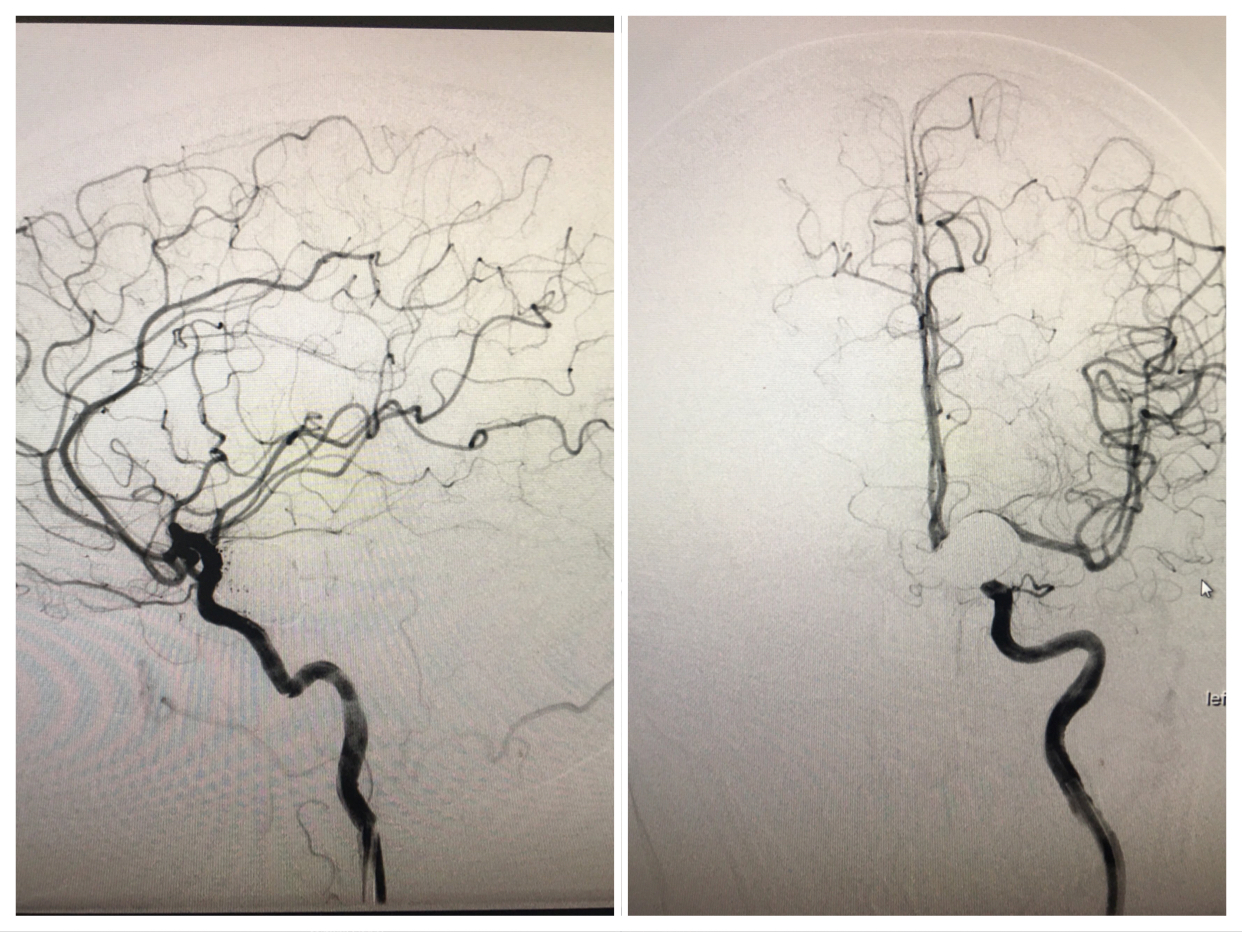

患者,女52岁,突发头痛头晕伴恶心到市人民医院就诊,CT提示珠网膜下腔出血,随收住神经外科。急诊在我院神经外科介入室行全脑血管造影,发现左侧颈内动脉后交通段一大小约23mmx17mm巨大动脉瘤。右侧大脑前动脉未见显示,供血区由左侧大脑前动脉代偿供血,后循环系统右侧椎动脉优势供血。

经科室会诊、与家属充分沟通,在上级专家指导下行颅内动脉瘤弹簧圈栓塞+支架植入术,术中支架释放顺利。术毕造影:瘤腔栓塞致密,瘤颈未见残留,支架贴壁良好,各级血管分支分布未见缺失,供血良好,手术顺利完美结束。目前患者已康复出院。